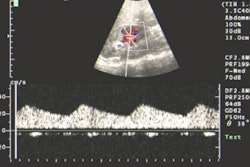

Whether this is marketing buzz or brisk business, only time will tell. But clearly, India is getting on the radiology map (yeah, that's why we're here) and not just on CT. Ultrasound contrast, which is new the world over, is also likely to come to India. The company bringing it here is Imaging Products (India) Pvt. Ltd.

You'll find all this and more on AuntMinnieIndia.com. Also look for clinical updates that feature imaging strategies for renal artery stenosis from the 6th Asia-Pacific Congress of Cardiovascular and Interventional Radiology. Last but not least, there is some key news on tuberculosis that concerns all our members from India.